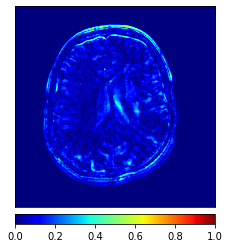

Moreover, Figs. 6 and 7 show the synthesized MR and CT images along with the errors between the real and synthesized images by different methods, respectively. It can be seen that the synthesized images by DC-cycleGAN are more identical to the real ones as compared with other methods. This indicates that effectiveness of SSIM and CE along with dual contrast in synthesizing images. In addition, the error between the groundtruth and synthesized MR/CT images by DC-cycleGAN is relatively less as compared with other methods.